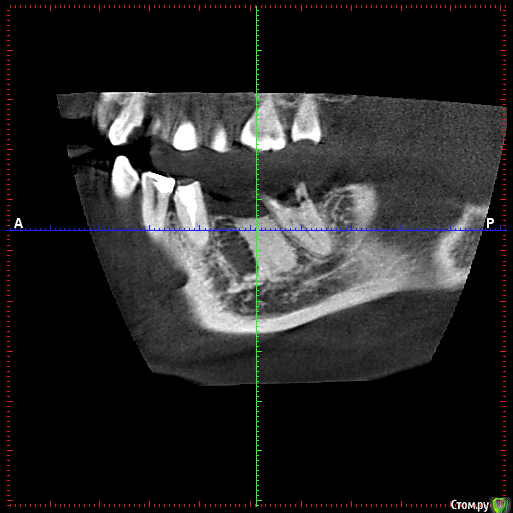

rezo47 Опубликовано 28 июня, 2016 Поделиться Опубликовано 28 июня, 2016 Добрый день коллеги! Планируется имплантация в области 46, 47, 47 уже удален. В области отсутствующего 46, жалоб нет, зуб удален более 20 лет назад. На кт образование, с четкими границами, по плотности сопоставимо с кортикальной костью. ВопросЧто это; Можно ли проводить имплантацию в данную область; Имплантация будет проводиться с забором кости на патогистологию.Кто сталкивался, или знает что с этим делать проконсультируйте Ссылка на комментарий

diesel87 Опубликовано 28 июня, 2016 Поделиться Опубликовано 28 июня, 2016 Похоже на участок очень плотной кости, типа остеомы или может при удаление зуба профессор какой сделал мощный сокет. Ссылка на комментарий

Vadsand Опубликовано 28 июня, 2016 Поделиться Опубликовано 28 июня, 2016 (изменено) Остеома. Возможно оставили корень зуба и организм так с ним поступил... интересно, какое там кровоснабжение...?) Изменено 28 июня, 2016 пользователем Vadsand Ссылка на комментарий

gum Опубликовано 29 июня, 2016 Поделиться Опубликовано 29 июня, 2016 Скорее всего это остеодисплазия. Формировать ложе под имплантат подождать 2 месяца, чтобы образовалась нормальная костная ткань с хорошей трофикой и только потом имплантат туда. Я бы поступил так Ссылка на комментарий